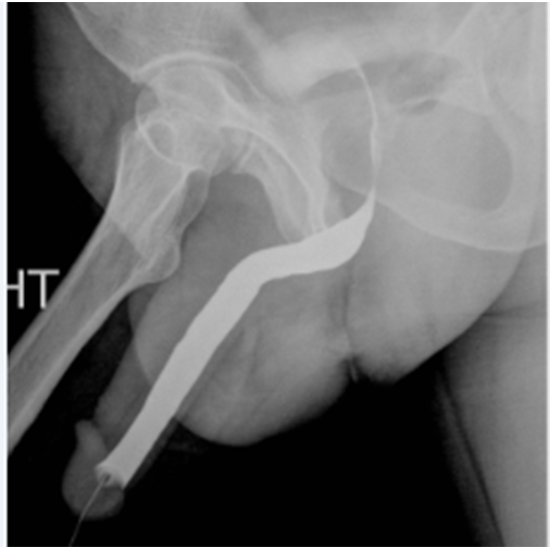

A Retrograde Urethrogram (RGU) X-ray analyses the urethra for non-visible structural problems. In a muscular tube, the urethra empties the bladder. This test is usually recommended for guys to diagnose urethral constriction caused by an enlarged prostate.

This test detects decreased urine flow due to prostate enlargement, urethral blockage, and urethral malignancies. Bloody or dark urine, bladder control loss, painful urination, and abdominal pain are narrow urethral symptoms.

The RGU helps diagnose urethral abnormalities and plans the appropriate treatment based on location and constriction. Five minutes are needed.